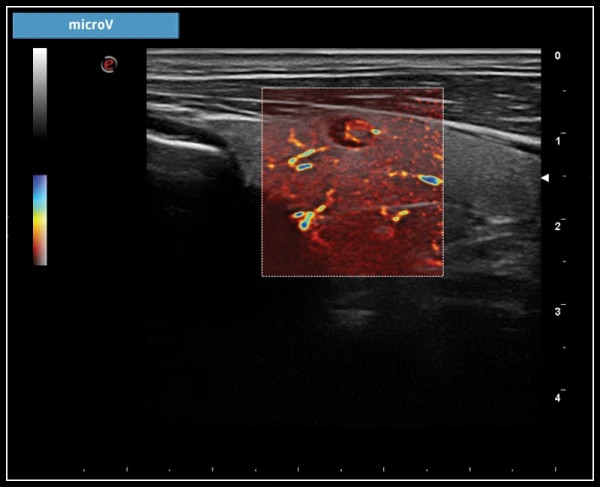

microV: Быстрое и неинвазивное исследование гемодинамики с высокой чувствительностью и высоким пространственным разрешением для оценки микроваскуляризации во всех клинических случаях.